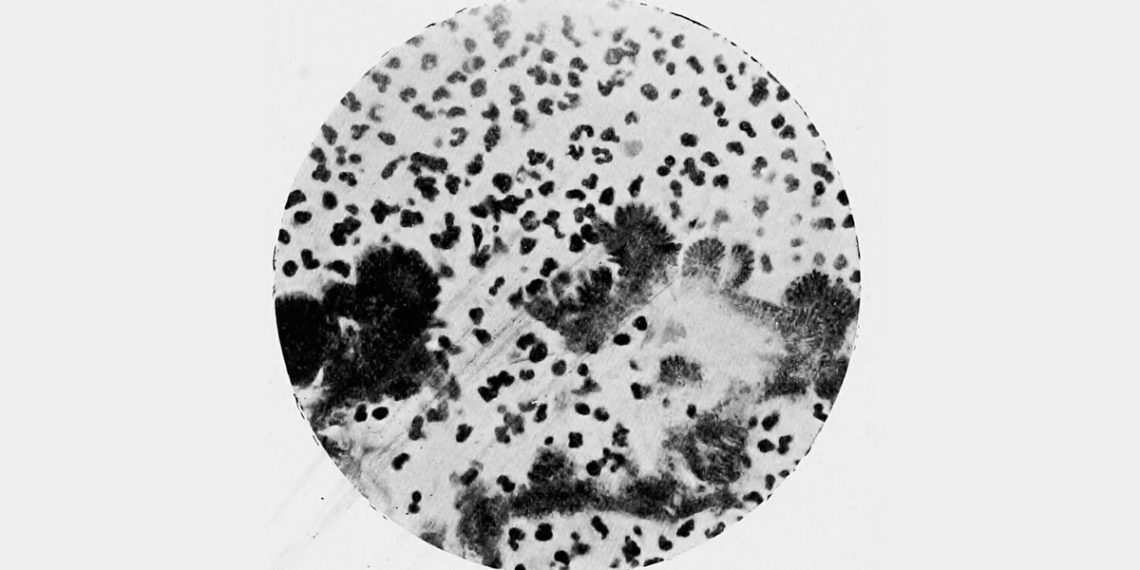

Complications and Long-Term Outlook of Actinomycosis can lead to serious and long-lasting health problems if left untreated, misdiagnosed, or if treatment is not completed. This chronic bacterial infection often progresses slowly, making early detection challenging. Once it spreads, the infection can create deep abscesses, form sinus tracts that discharge pus, and cause extensive tissue damage.

In severe cases, these sinus tracts remain open for months, draining continuously and becoming sites of secondary infection. When the bacteria invade deeper structures, they can infect bones—particularly the jaw or skull—leading to a painful condition known as osteomyelitis. Without intervention, actinomycosis can spread to the chest, lungs, abdomen, pelvis, and even the brain. These complications may result in long hospital stays, surgeries, and in rare cases, life-threatening sepsis.

Facial actinomycosis can leave disfiguring scars due to chronic swelling, skin breakdown, and repeated abscesses. This form often follows dental infections or poor oral hygiene and tends to persist unless treated aggressively with long-term antibiotics and, in some cases, surgery.